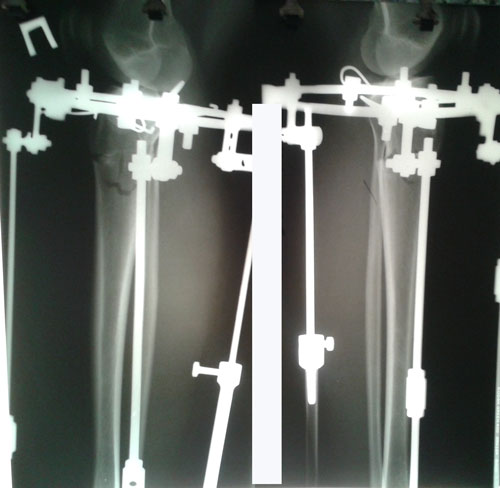

Дата операции 15.03.2017г.

Дата снятия аппаратов 23.06.2017г.

Срок лечения 97 дней.